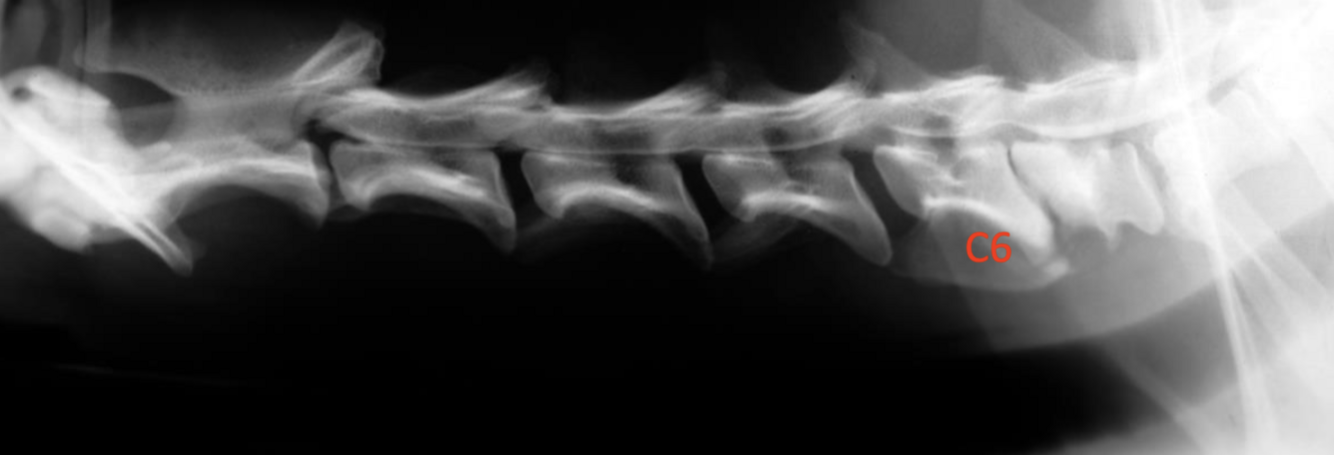

What is shown on this myelogram?

A

ventral, extradural compression at C5 to C6 and C6 to C7

How can extension and flexion of the neck be used in cervical spondylomyelopathy diagnosis?

compression may be exacerbated with either flexion or extension and show up better on imaging